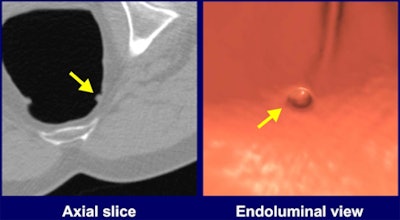

| A polyp (7-mm sessile adenoma in the rectum; false negative on CTC in the original trial) initially missed by two out of four radiologists in the study, but detected with CAD. Images courtesy of Kenji Suzuki,PhD. |